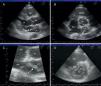

On return to the CCU, the patient experienced complete relief of chest pain and ST-segment normalization on the ECG. Nonetheless, her oxygen saturation level was still 90% despite high-flow oxygen by mask. A full transthoracic echocardiogram examination was then performed. A mass consistent with a thrombus was noted in the left atrium, appearing to arise from a redundant interatrial septum, while the right ventricle was moderately dilated with positive McConnell sign and the interventricular septum was displaced into the left ventricle, which was D-shaped in short-axis view (Figure 3). The pulmonary artery was dilated and the flow across the pulmonary valve suggested severe pulmonary hypertension with pulmonary artery systolic pressure estimated at 70 mmHg. In apical 4-chamber view, color flow imaging of the interatrial septum showed a right-to-left shunt. It was then decided to perform transesophageal echocardiography (TEE) to better characterize the relationship of the mass with the interatrial septum and its embolic potential, and also to look for masses in the right atrium. TTE showed a long thrombus that appeared to be attached to the atrial septum in the region of the foramen ovale. Color flow imaging was consistent with a patent foramen ovale (PFO) and the atrial septum was aneurysmatic. The thrombus had a snake-like movement inside the left atrium and its distal end was freely mobile, prolapsing through the mitral valve (Figure 4). No mass was observed in the right atrium or pulmonary arteries. Thoracic computed tomography angiography revealed bilateral thrombi in the main and lobar branches of the pulmonary artery (Figure 5).

(A) parasternal long-axis view; (B) parasternal short-axis view of the aortic valve; (C) zoom of short-axis view; (D) D-shaped left ventricle. Ao: aorta; IVS: interventricular septum; LA: left atrium; LV: left ventricle; RA: right atrium; RV: right ventricle; RVOT: right ventricular outflow tract; Tr: thrombus.